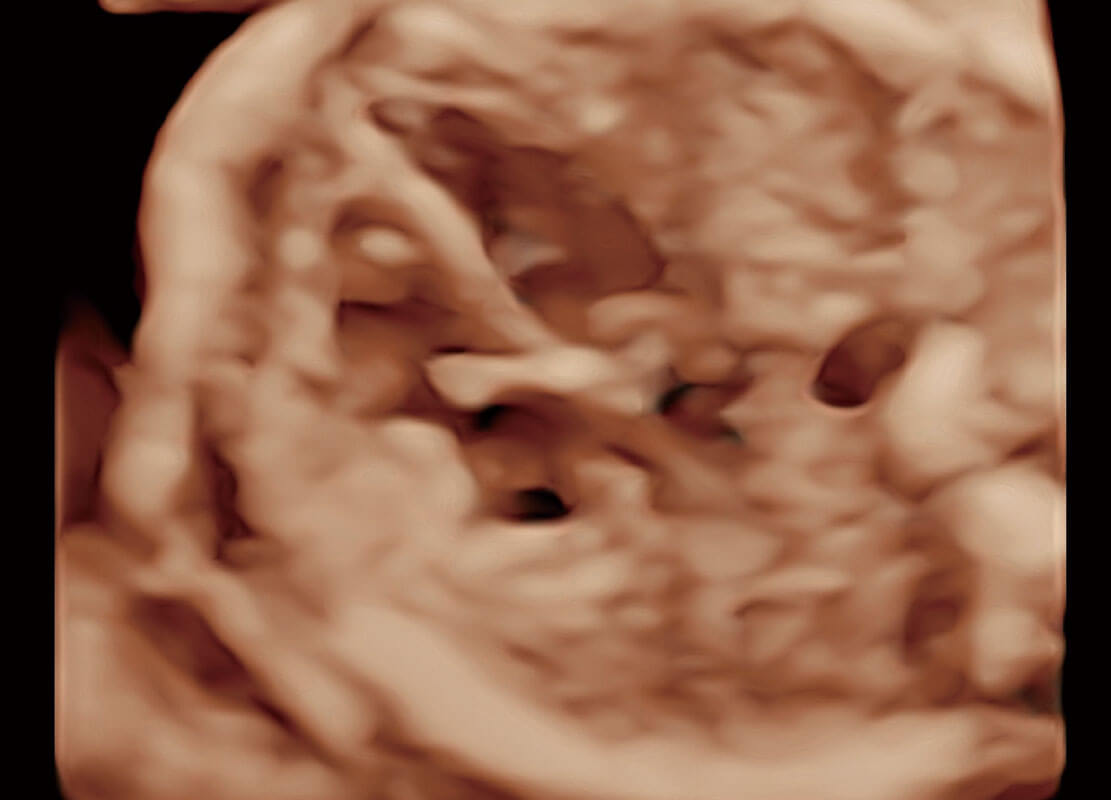

腔内三维-宫内节育器

腔内三维-光影成像